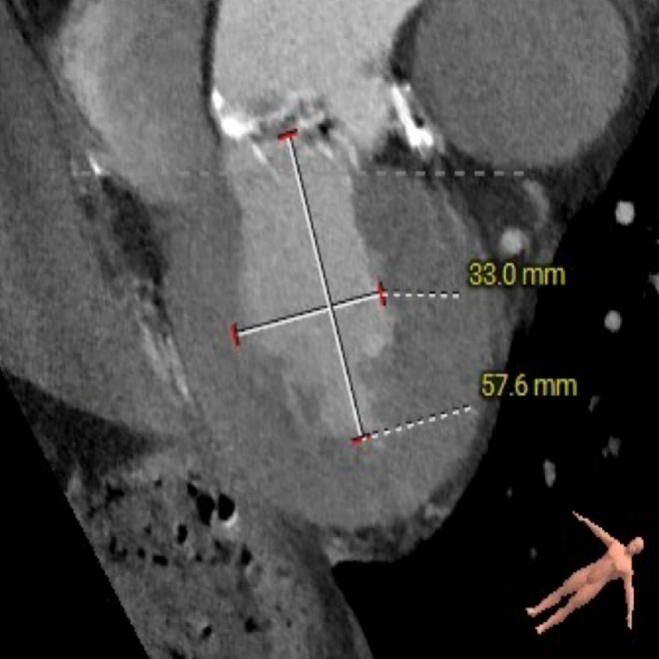

主动脉根部测量

ANNULUS

SOV DIAMETER

LVOT

STJ

瓣环水平夹角

LEFT VENTRICLE

CT数据显示该患者为三叶式主动脉瓣。

主动脉瓣瓣环周长66.2,平均周长径 21.1mm,SOV:32.2mm*36.4mm*34.1mm,瓣叶增厚,瓣上钙化分布不均,主动脉瓣环水平夹角67度,横位心。